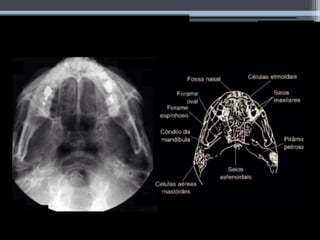

Axial de Hirtz

• #21 Sinonimos: submento vértice Paciente sentado ou em decúbito dorsal. Elevar o queixo superextendendo o pescoço até que a linha infra orbito meatal (LIOM) ESTEJA PARALELA Á MESA. A CABEÇA DEVE ESTAR APOIADA NO VÉRTICE DO CRANIO. CUIDADO PARA NÃO HAVER ROTAÇÃO. RAIO CENTRAL PERPENDICULAR Á LIOM, CENTRADO A UM PONTO MÉDIO ENTRE OS ANGULOS MANDIBULARES.

• #22 Seios maxilares, esfenoidais, células etmoidais, fossas nasais. Pirâmides petrosas visualizadas simetricamente.